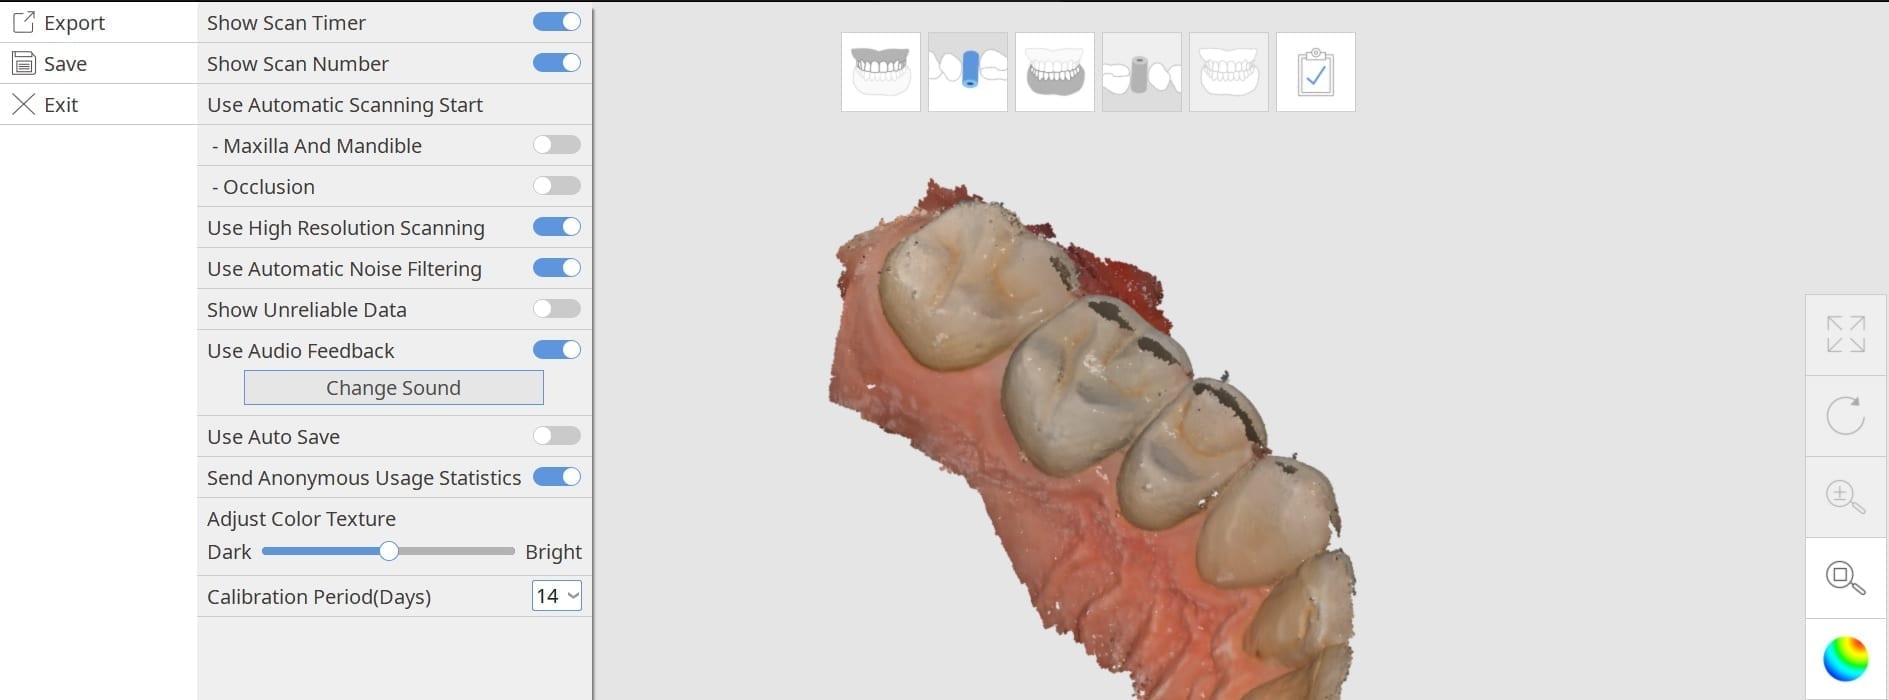

Settings for Meditlink Scanning

August 25, 2018[table id=12 /] Video 1- Show Unreliable Data and Automatic Noise filtering (High Resolution Scan off) Video 2- Use Automatic Noise filtering / Do Not Show Unreliable […]

[table id=12 /] Video 1- Show Unreliable Data and Automatic Noise filtering (High Resolution Scan off) Video 2- Use Automatic Noise filtering / Do Not Show Unreliable […]